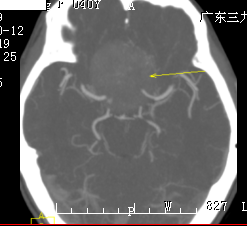

王女士,40岁, 5年前开始出现右眼视物模糊,1年前开始出现左眼视物模糊,为求治疗,来我院就诊。病人由神经外一科接诊,完善相关术前检查,结果示:肿瘤组织包绕神经、动脉,考虑到手术的风险性,科室组织专家反复进行术前讨论,拿出最佳的手术方案,由神经外一科主任张良主刀完成。

行全麻下右侧扩大翼点入路鞍结节脑膜瘤切除术。术中见右侧视神经、颈内动脉被肿瘤包绕,肿瘤血供丰富,肿瘤起源于鞍结节及鞍隔。术中全切肿瘤,神经、血管、垂体柄完好。术后病理示:鞍区脑膜瘤,部分为过渡细胞型,部分为血管瘤型脑膜瘤,WHO I级。术后左侧视力同术前,右侧视力较术前稍差。 经系统的治疗后康复出院。

血管瘤型血供丰富,控制术中出血尤其重要。术前通过影像学了解肿瘤的供血情况,术中优先对肿瘤基底部(鞍结节处)进行处理,阻断其血供,从而减少术中出血,鞍隔处不要急于处理,以免损伤垂体柄。之后再对肿瘤进行分块切除,应先从无重要结构的中心部位进行分块切除。剥离小块肿瘤时应谨慎,避免拉断其周围的神经、血管等,还应尽量减少对视神经的牵拉,切勿损伤视器的血供,同时手术应保持在蛛网膜下腔内操作,尽量避免直接损伤视神经。